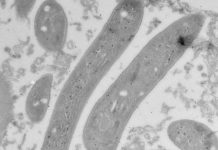

Study: When malaria parasites trick liver cells to let themselves in (TDnews)

Photo: Electron microscopy image of sporozoites with EXP2 labeling.